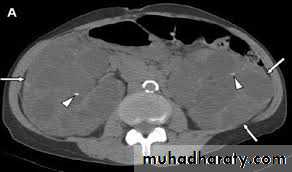

Autosomal dominant (adult) polycystic kidney disease (ADPKD)

ADPKD is an autosomal dominant inherited disorder leading to the development of multiple expanding renal parenchymal cysts.The kidneys reach an enormous size due to multiple fluid-filled cysts and can easily be palpated on abdominal examination. Expansion of the cysts results in ischemic atrophy of the surrounding renal parenchyma and obstruction of normal renal tubules.

End-stage renal failure is inevitable and occurs around the age of 50 years.